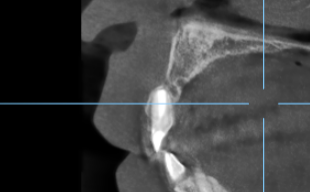

多発性歯根嚢胞を精密根管治療、歯根端切除術を行なった症例

治療前